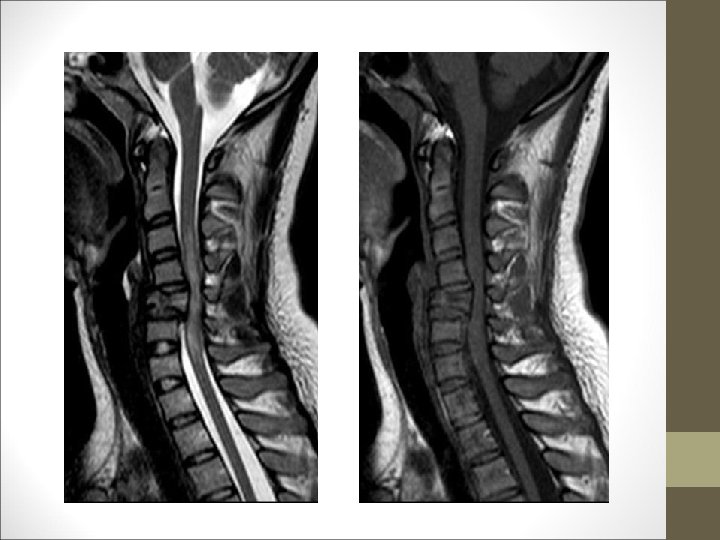

TC Desplazamientos de fragmentos óseos ¿Algo mas? Desplazamientos discales y lesiones ligamentosa FACULTAD DE MEDICINA DEPARTAMENTO DE CIRUGÍA NEUROCIRUGÍA RM

¿Primer paso en el tratamiento? Reducción Cerrada Tracción cervical FACULTAD DE MEDICINA DEPARTAMENTO DE CIRUGÍA NEUROCIRUGÍA Evaluación de estabilidad segmento C 3 -C 7 : -Daño neurológico -Daño importante del complejo ligamentario -Desplazamiento anterior de un cuerpo > 3, 5 mm (20%) -Angulación de vértebras adyacentes de más de 11º -Rotura ligamentosa posterior importante -Lesión del disco